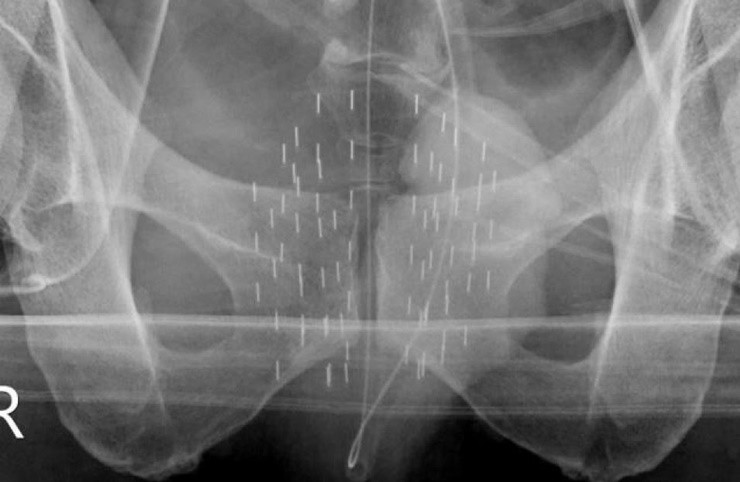

브라키테라피란 국소 전립선암 환자에게 시행되는 방사선 치료 방식 중 하나로, 전립선 조직 내부에 방사성 동위원소를 삽입하여 암세포를 사멸시키는 방법이다. 구체적으로는 바늘을 이용해 전립선에 다수의 방사성 동위원소(예: 요오드‑125 등)를 영구 삽입하는 방식으로, 삽입된 동위원소들은 시술 직후부터 작동을 시작해 약 3~4개월간 지속적으로 방사선을 조사하며 암세포 제거를 돕는다.

조 교수는 완벽한 시술을 위해 완벽한 치료 계획을 세운다. 한번 삽입이 끝난 방사선동위원소의 위치를 되돌릴수 없기 때문에 정확한 치료계획 및 맟춤형 설계로 유명하다. 전립선암의 경우, 회음부를 통해 삽입할 니들(바늘)의 위치와 각도를 정확히 계획하여 고정밀 TRUS (Transrectal Ultrasound) 가이드 하에 삽입 경로가 정해진다.